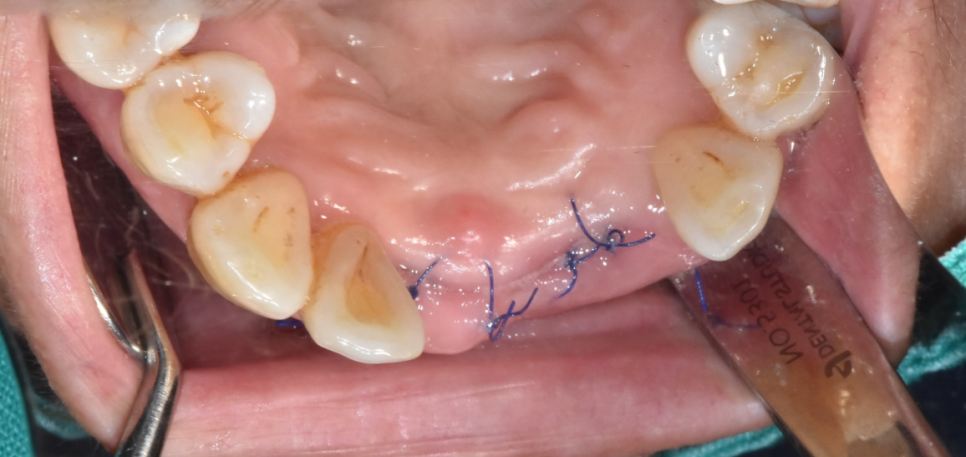

우선 윗니 앞니 흔들림으로 내원하신게

잇몸 뼈가 없었기 때문에

임플란트 시술 시 잇몸 뼈를 두둑하게 채워넣었습니다.

앞니의 경우 잇몸 볼륨이 빵빵해야

나중에 보철을 해도 예쁘거든요~

잇몸 뼈가 푹 꺼져 보이면 나이가 들어 보일 수 있고

보기 싫어집니다.

231107

수술 직후 사진입니다.

일반적으로 실밥은 임플란트 수술 후 일주일 정도 지나면

제거해드립니다.

앞니의 경우 잇몸이 얇기도 하고

워낙 뼈 이식을 두툼하게 해두어

오늘 환자분은 2주 정도 기다렸습니다.